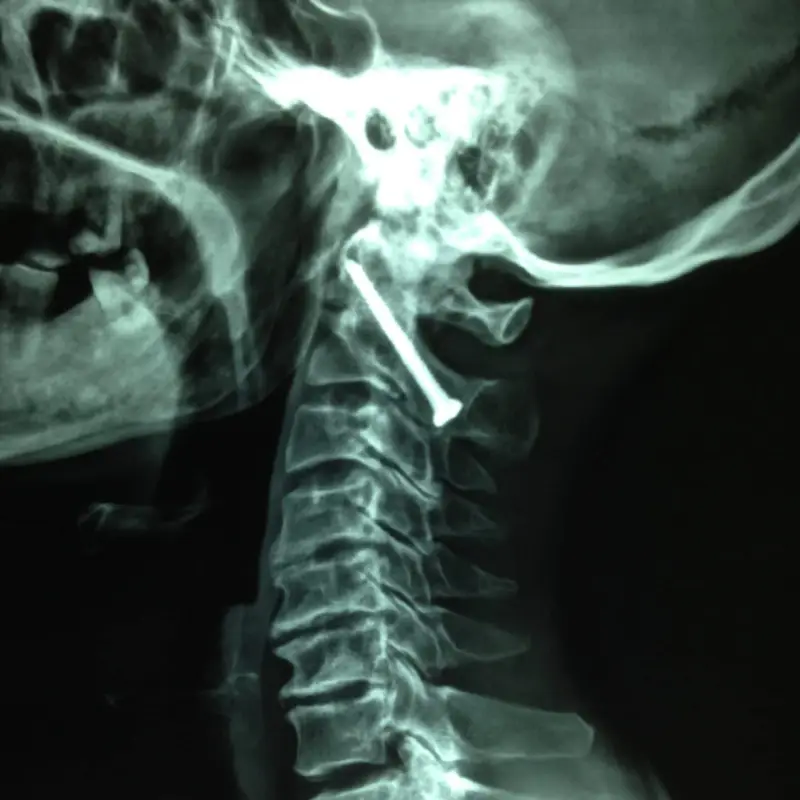

C1-C2 Transarticular Screw